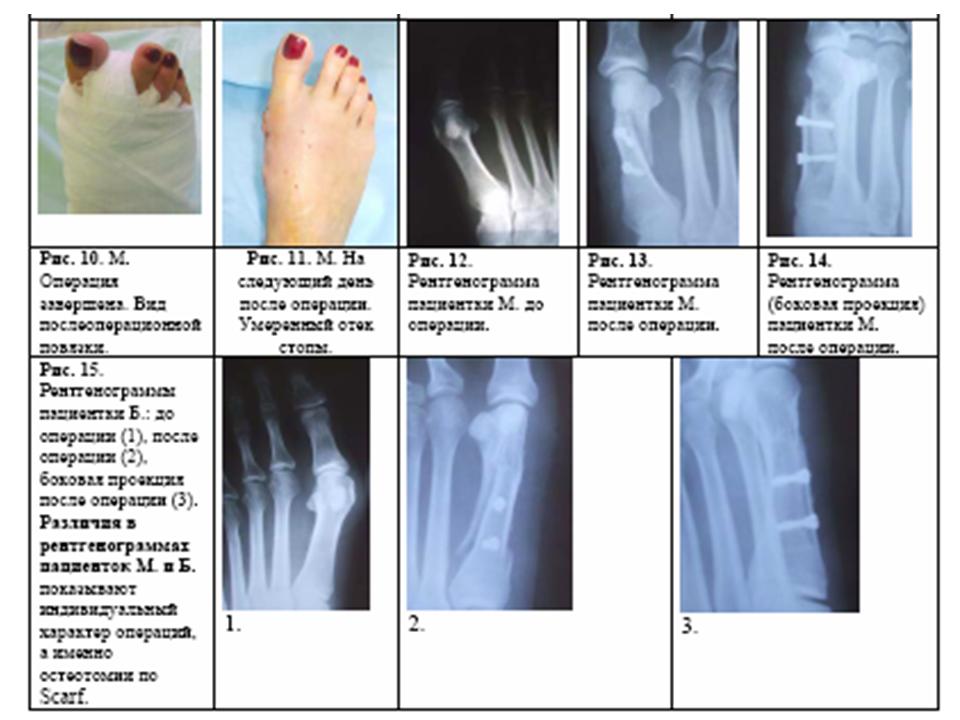

1.

Hallux valgus

(HV)

и остеотомия

Scarf

(Рисунки 1-6)

Иллюстрации

остеотомии Scarf

(собственные фотографии

этапов наших операций). Мы показываем

здесь лишь часть этапов операции, но и

это позволяет представить истинную

сложность ее, но и высокую эффективность

по коррекции деформаций переднего отдела

стопы с Hallux

valgus. Далее мы показываем и

этапы операции и рентгенографический

контроль.

2. Hallux valgus

(HV) и

остеотомия Scarf

(Рисунки 1-15)